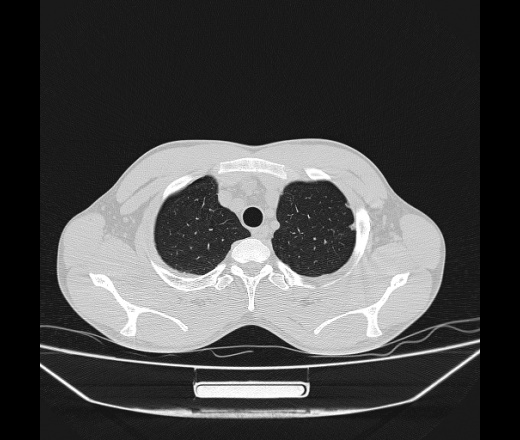

Молодой парень 18 лет, призывник, при прохождении ФЛС на верхушек левого легкого выявили очаги средней интснисвности с нечеткими контурами, тяжи. Сделали бок и томограммы 6-7-8. Везде описывают как очаговый твс. Вижу только перибронхиальный фиброз. Что за изменения в бронхах, указано нижи стрелками, тоже перибронхиальный?

Не стал бы говорить об очагах. Акцентировал бы не на фиброзе, а на тракционных бронхоэктазах. Не обязательно они результат tbc бронхов, но проверить не помешает.

Иван, пациент ведь уже "направлен с ОПТД", так?surprise Возвращайте его назад с заключением о возможном микобактериозе. Остаточные поствоспалительные ( посттуберкулёзные?) в дифряд.Очаговый твс с неясной активностью они уже себе "нарисовали", как я поняла.

+1 за микобактериоз.